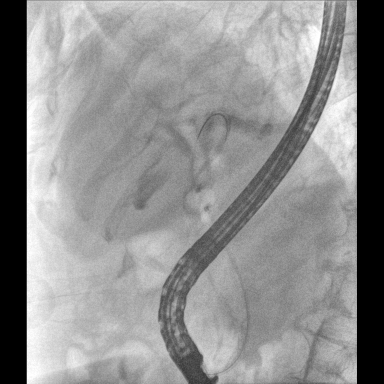

具備血管造影及數(shù)字減影(DSA)、路徑圖(Road-map)、透視、攝影等功能。 廣泛適用于介入科、血管外科、腫瘤科、消化內(nèi)科及骨科等多個臨床科室,典型應(yīng)用包括:TACE(肝腫瘤栓塞與化療灌注術(shù))、心臟起搏器置入術(shù)、四肢動脈造影術(shù)、下肢靜脈濾器置入術(shù)、ERCP(經(jīng)內(nèi)鏡逆行胰膽管造影術(shù))等。

Clinical picture

臨床圖片